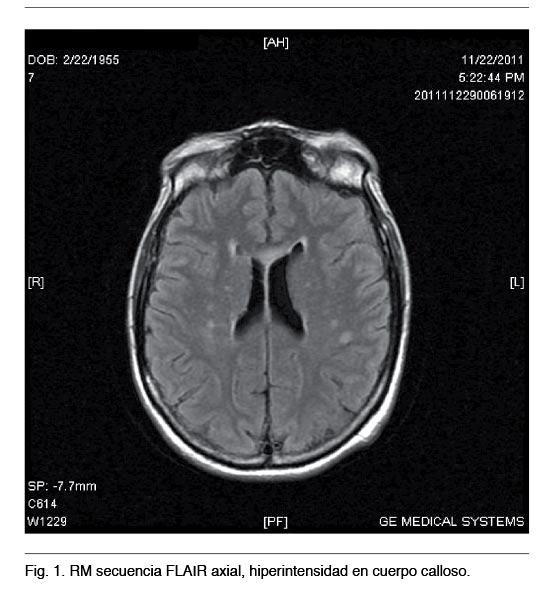

La imagenología, especialmente la Resonancia Nuclear Magnética (RNM), ha contribuido a mejorar el diagnóstico por las imágenes características de afectación del cuerpo calloso (1) que ofrecen las diferentes secuencias; aumento de señal del cuerpo calloso en T2 y FLAIR o zonas quísticas en T1 sagital con disminución de señal (3). Las alteraciones en la RNM pueden extenderse a otras regiones de la sustancia blanca (1,11). La Tomografía Computada (TC) craneal puede captar una hipodensidad en la rodilla del cuerpo calloso pero dado que los cortes suelen ser exclusivamente axiales no es infrecuente que la alteración del cuerpo calloso pase desapercibida (12). Los análisis de casos a través de la imagenología han revelado varios patrones, incluyendo lesiones dispersas o quistes observados a lo largo del cuerpo calloso, áreas cercanas (comisuras anterior y posterior, vías de la sustancia blanca, etc.) y el centro semioval. En algunos pacientes la EMB puede estar asociada a daño cortical, en general en el área frontal lateral y lóbulo temporal, principalmente en la tercera capa cortical. En dichas regiones las neuronas son sustituídas por células gliales (2). En 1939 Morel describió esta esclerosis laminar cortical, denominada esclerosis laminar cortical de Morel (2).

RNM mostró en diferentes secuencias lesiones típicas en cuerpo calloso y tronco encefálico (Figuras 1 y 2).

Este caso clínico a forma de presentación subaguda, muestra varias similitudes con respecto a los publicados en la literatura (18-20): el antecedente de alcoholismo crónico, síntomas y signología neurológica poco característica y el diagnóstico por neuroimagen con la afectación típica del cuerpo calloso y el compromiso de otras estructuras neurológicas.

En cuanto a las diferencias con la mayoría de los casos revisados se presentó en el sexo femenino con lesión pontina por RM, sin evidencia clínica de dicha afectación (21,22).